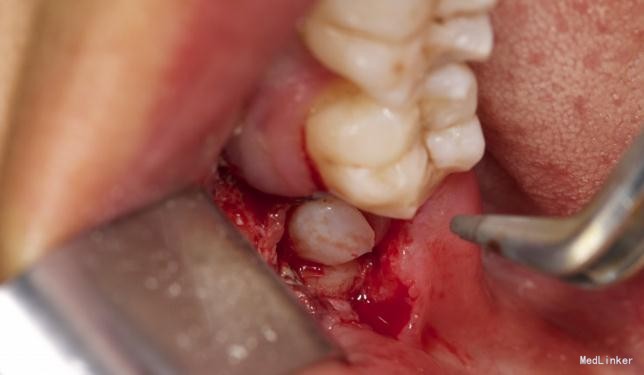

患者,男,25岁,要求拔除左下颌水平阻生牙齿,平素体质一般,无药物、食物过敏史,无高血压、心脏病等系统病史

拔除术

挺好的病例,图片也很清晰,牙齿分的很好,我之前拔过类似的牙,牙齿分开后近中撬不动,最后又T型分开近中后才弄出来

详尽的病例,值得学习。水平阻生的智齿应该尽早拔除,以免后患,极容易在7和8之间形成食物嵌塞而导致7的远中邻面龋坏。8远中的盲袋也易导致冠周炎